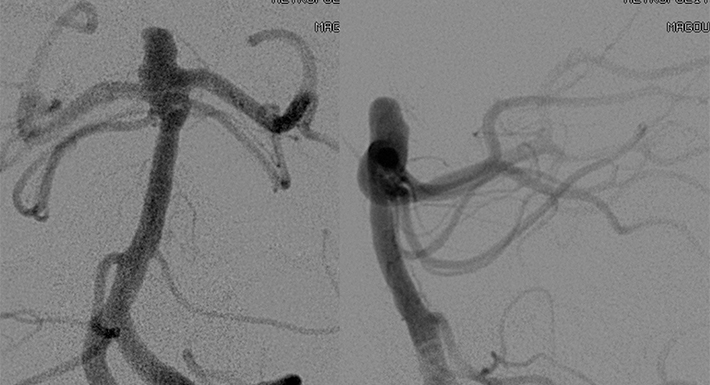

Εμβολισμός ανευρυσμάτων εγκεφάλου με τροποποιητές ροής (Flow - Diverter Stents, FDS)

Τα μεγάλα και ευρέως αυχένος ανευρύσματα, όπου στον αυχένα του ανευρυμσατικού σάκκου συμμετέχει μεγάλο τμήμα της περιμέτρου του θυγατρικού αγγείου, αποτελούν μιά θεραπευτική πρόκληση. Χωρίς θεραπεία έχουν 5ετή κίνδυνο ρήξεως 14.5%-40% ανάλογα με την εντόπιση.

Ο εμβολισμός με GDC coils ακόμη και με τις περισσότερο εξελιγμένες τεχνικές (balloon or stent-assisted coiling, complex and biological coils) δεν κατάφερε να προσφέρει οριστική, πλήρη και διαρκή εξάλειψη από την κυκλοφορία, με αποτέλεσμα οι ασθενείς να είναι ευάλωτοι σε επανασηραγγοποίηση και αναιμορραγία.

Τα πρώτα αυτο-εκπτυσσόμενα ενδοκράνια stents σχεδιάστηκαν με σκοπό το stent-assisted coiling, ώστε να υποστηρίξουν την τοποθέτηση coils μέσα στο ανεύρυσμα. Είχαν μεγάλους πόρους ώστε να επιτρέπουν την διέλευση του μικροκαθετήρα, και χαμηλή κάλυψη από μέταλλο με αποτέλεσμα το αιμοδυναμικό αποτέλεσμα της τροποποίησης της ροής να είναι περιορισμένο.

Η νέα γενιά των flow-diverter stents (FDS),

έχουν πυκνή κάλυψη από μέταλλο, με αποτέλεσμα να τροποποιούν την δυναμική της ροής του αίματος κατά μήκος του ανευρυσματικού αυχένος και να προάγουν την ενδο-ανευρυσματική θρόμβωση. Το FDS προοδευτικά ενσωματώνεται στο τοίχωμα του αγγείου μέσω της ανάπτυξης νεο-ενδοθηλίου που έχει ως αποτέλεσμα την πλήρη ανατομική εξάλειψη του ανευρύσματος από την κυκλοφορία. Καθώς ο ανευρυσματικός σάκκος θρομβώνεται, και αργότερα απορροφάται, δευτερογενώς εξαλείφονται τα πιετσικά φαινόμενα (mass effect) στις γειτονικές δομές του εγκεφάλου και αποκαθίσταται η εξω-αγγειακή ανατομία. Το ενδιαφέρον είναι ότι η ροή προς τους φυσιολογικούς κλάδους διατηρείται, όπως και η βατότητα των διατιτραινόντων κλάδων που εκφύονται από το θυγατρικό αγγείο.